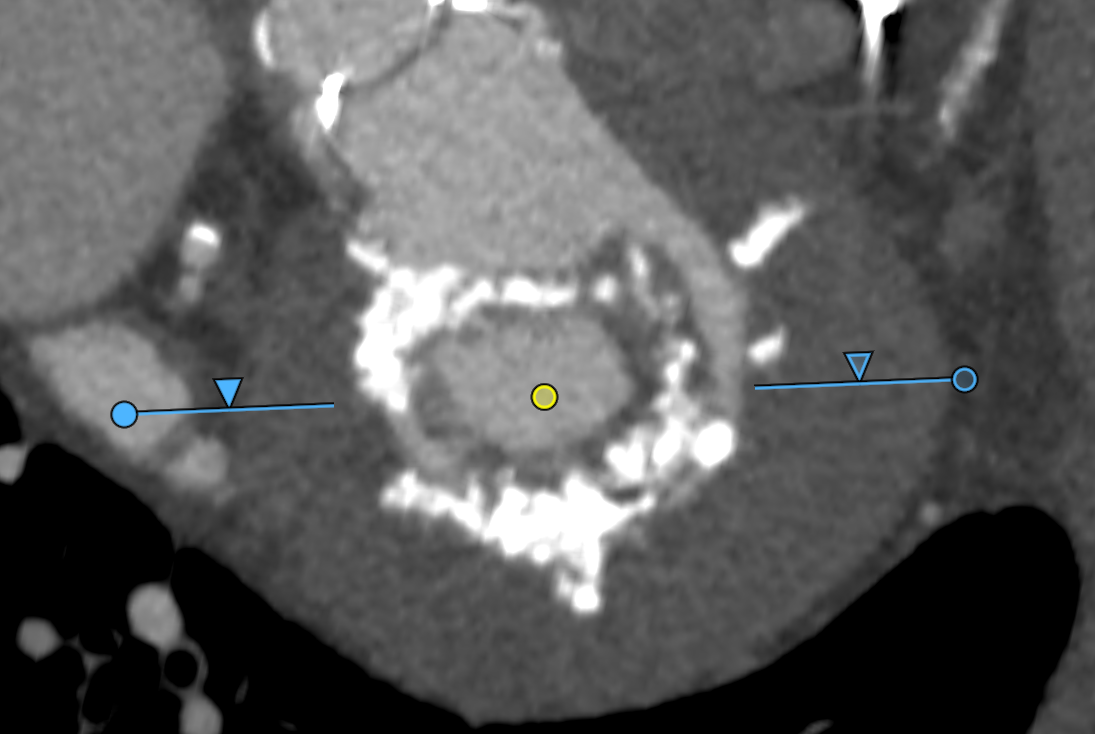

1. Cardiac CT plays a central role by providing detailed measurements of the mitral annulus, assessing the predicted neo-LVOT area to avoid left ventricular outflow tract obstruction, and identifying calcium distribution across the annulus and leaflets.

Planning software like 3mensio Structural Heart can can streamline TMVR planning by providing accurate annular sizing, neo-LVOT area prediction, assessment of annular and sub-annular calcification, and simulation of both transapical and transseptal access paths. This comprehensive imaging and planning workflow enables device selection, positioning, and risk management, particularly in anatomically challenging cases.